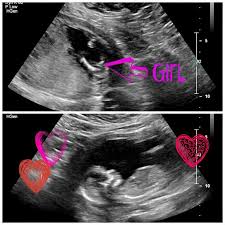

If you have cvs at 10 weeks the results will reveal your baby s sex by 12 weeks. This is the most common way to determine your baby s sex and most low risk pregnancies find out the baby s sex this way between the 18th and 22nd week of pregnancy. Moms to be who undergo amniocentesis a prenatal test that s used to check for certain genetic problems usually around 16. Most doctors schedule an ultrasound at around 18 to 21 weeks but the sex may be determined by ultrasound.

Ultrasounds may reveal sex organs by 14 weeks but they aren t considered fully accurate until 18 weeks. However gender scans are generally available privately from 16 weeks. The ultrasound image can help detect fetal developmental abnormalities the baby s size and growth as well as the gender of the baby most mothers to be have an ultrasound around 18 to 20 weeks that shows the gender of the baby but ultrasounds are sometimes done at 16 weeks. But as early as seven weeks you can know your baby s gender through blood testing.

Getty contributor the nub theory. The gender of your baby is revealed at your second scan between 18 and 21 weeks but there s another test people use to determine if it s a boy or girl credit. The chinese lunar calendar can predict a baby s gender based on the mother s age when they conceived and the month of conception. Since an ultrasound creates an image of your baby it can also reveal the sex of your baby.